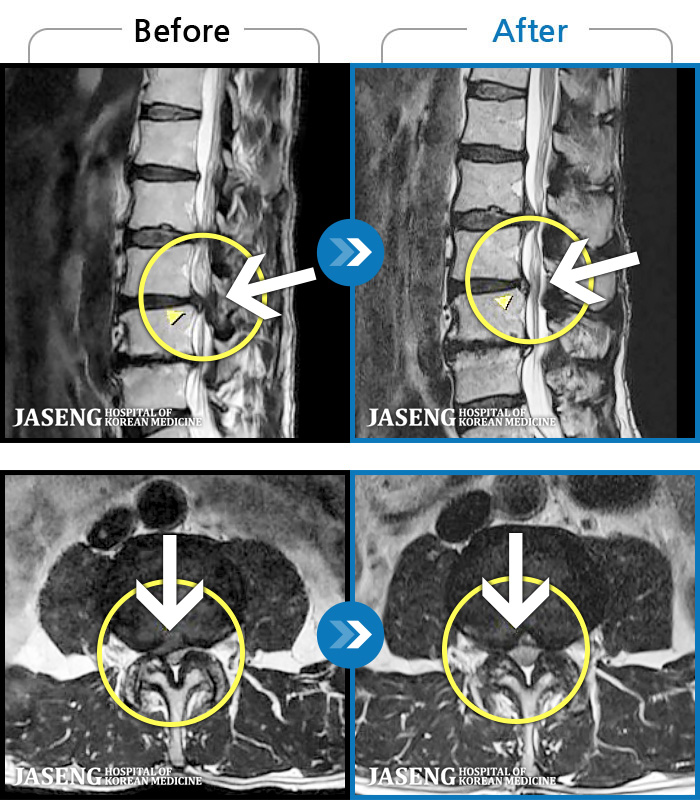

- MRI ġ

97 MRI ũ ʸ Ȯϼ.

MRI ġ

Ƹ ϰ ־.

[õ] 25.03.18~25.07.22

ȯںп Ǹ ǿ ԿǾ, ο ġ ۿ Ƿ ġḦ Ͻñ ٶϴ.